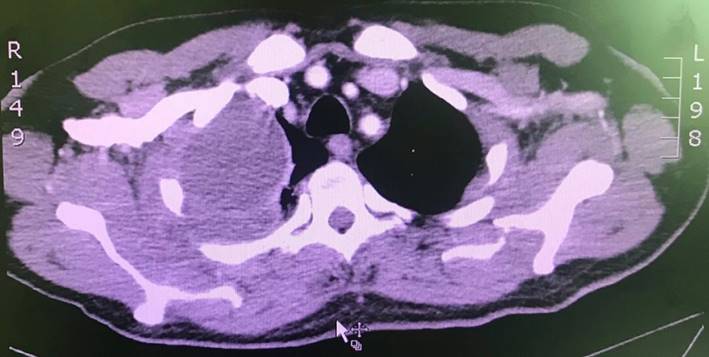

Ante los hallazgos en la radiografía simple, se decidió complementar el estudio con una TAC de tórax con contraste, que reportó colecciones pleurales bilaterales con extensión a la pared del tórax (con compromiso de la musculatura intercostal y escalénica en el lado derecho; en el lado izquierdo estaba comprometido el pectoral) en relación con Empiema Necessitatis (Figura 3, Figura 4).